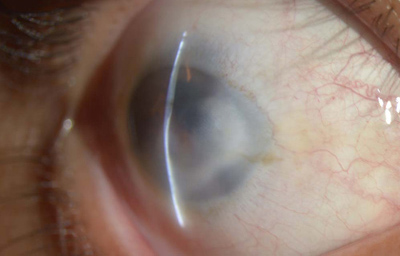

Aniridia completa, catarata y distrofia corneal de la aniridia

Archivo Dr. Francisco Barraquer

Caso de paciente con Coloboma en un ojo y Aniridia en el contralateral

OD

Archivo Fotográfico Dr. Francisco Barraquer

OI

Archivo Dr. Francisco Barraquer